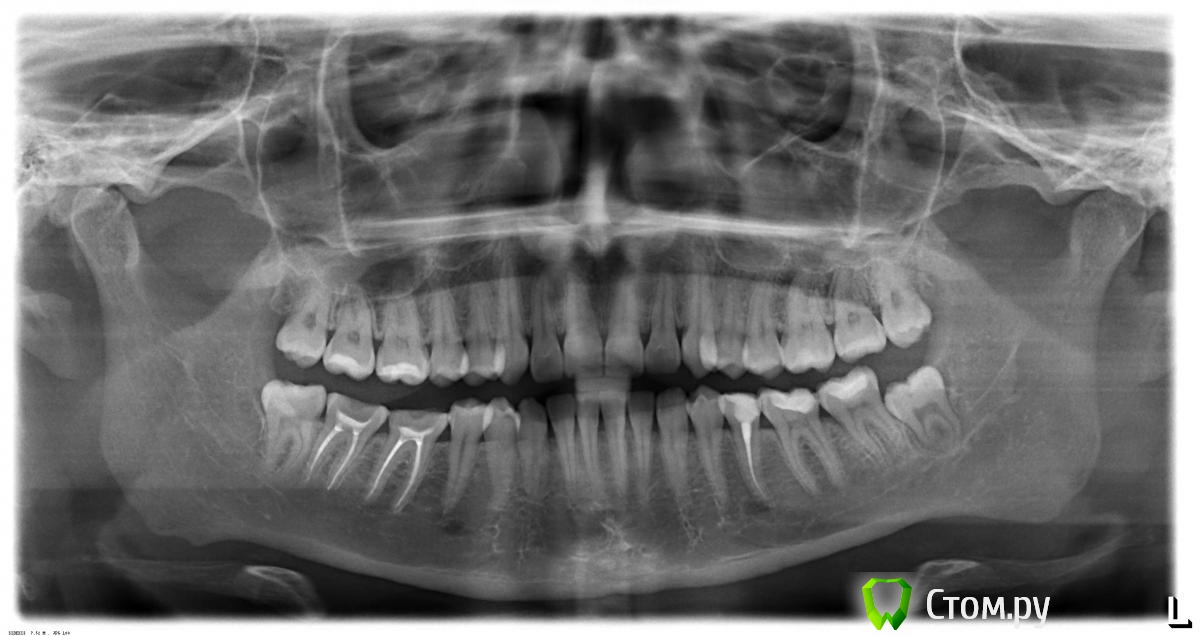

Екатерина_М Опубликовано 9 декабря, 2013 Поделиться Опубликовано 9 декабря, 2013 (изменено) Добрый день.Подскажите, пожалуйста. Удалили нервы в 6 и 7 зубах на нижней челюсти справа. В 6-м зубе запломбировали каналы 30 ноября, в 7-ке - 7 декабря. Пломбировали, судя по расшифровке счета, методом латеральной конденсации.С 6-м зубом по ощущениям все хорошо - он почти не болел.С 7-м же похуже - было больно пломбировать один из каналов. Сразу после пломбировки, как отошла анестезия, зуб болел довольно сильно, пришлось выпить Нурофен. В воскресенье 8 декабря зуб сам по себе почти не болел, но был болезненным при надавливании. И после того, как я на него давила, оставался болезненным в течении какого-то времени. Сегодня, в понедельник 9.12, ситуация почти такая же - чуть меньше болит при надавливании, но жевать по-прежнему на правой стороне больно.На сколько это нормально? Стоит ли надеяться, что болезненность пройдет? Оцените, пожалуйста, на сколько хорошо запломбированы каналы. Потому что скоро на эти зубы буду ставить вкладку, потому туда будет тяжело залезть.И подскажите, еще пожалуйста, что стоит делать с остальными зубами. За последний год прорезались 3 зуба мудрости, хочу их удалить, стоит ли? http://s019.radikal.ru/i638/1312/19/e8d80a4c5686t.jpg Заранее спасибо. Изменено 9 декабря, 2013 пользователем Екатерина_М Ссылка на комментарий

red_butler Опубликовано 12 декабря, 2013 Поделиться Опубликовано 12 декабря, 2013 Екатерина_М по снимкам вроде все неплохо, боли должны пройти. Если не пройдут - повторное лечение 4.7; Мудрые зубы если беспокоят - удаляйте, Только по ОПГ явных показаний к удалению нет, нужен очный осмотр. Коронки на зубы 4.7 4.6 3.5 ; периодически проф. гигиена Ссылка на комментарий